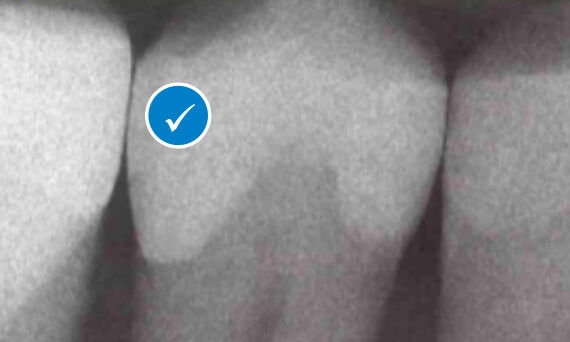

Palodent matrix systems help you achieve reliable isolation with a tight gingival seal.

The innovative design and integrated tightener of Palodent 360 help to achieve optimal contacts and anatomically natural contours, all with just a twist of your fingers.

Palodent 360 is compatible with all commonly used dental composites, adhesives, etches, amalgams and other Dentsply Sirona Class II Solution products. For better restorations, faster and easier than you ever thought possible.